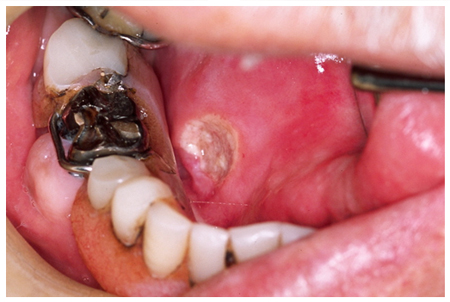

口腔癌について①小倉北区の歯医者「ますだ歯科クリニック」。

こんな症状が実は病気のサイン?:口腔内の異変と早期発見・治療の重要性口腔がん検診・舌がん検診予約を歯科医院で一般社団法人口腔がん撲滅委員会。

口内炎かどうか気になっている患者様が増えています岐阜県関市のえんどう歯科・矯正歯科クリニック。充実の最新設備。

舌の口内炎はがんの可能性?舌がんと口内炎の見分け方や治療方法を解説 - 口腔外科DOC。